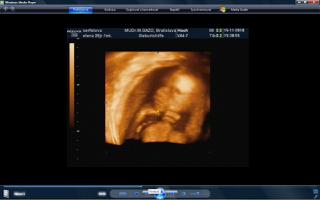

vcera som mala poradnu a teda dopadla pre mna dost prekvapujucu. mala je uz mesiac otocena dolu hlavickou a tlaci sa a tlaci. krcok sa mi zacal skracovat, ale zatial sa neotvara. a aby toho nebolo malo, tak mam aj iritabilnu maternicu. buducu nedelu idem do nemocnice na premeranie krcka a uvidi sa, co bude. aspon, ze ju uvidime 3D potvorku malu nedockavu 🙂 do mesiaca mi zrejme bude treba zaviest pesar.. tooolko radosti naraz a to som povodne vobec nemala mat poradnu, kedze som povodne dosla len s babkou na kontrolu..tak vysetrila aj mna.

caute baby. uz som tu dlho nebola. nejako nestiham. My sme uz boli na tiez na 3D a zase mala mala rucicky pred tvarickou ale daco bolo aj vidno. takze sme zistili, ze sa podoba na muza, teda aspon ten nos usta. Ma skoro 500 g takze je asi o tyzden posunuta neskor.Ak sa mi bude dat tak pridam dake fotky z toho dvd co som vybrala. Inac ja som kupovala tehotenske pancuchy v Brendone v Ba za 4 Eura. teda tenke ale mali tam aj hrubsie a tie stali 15 eur. Ja tiez rozmyslam rodit v ruzinove ale asi skor na Kramaroch. to mam blizsie domov. Ja si doplacam od marca dobrovolne nemocenske poistenie k povinnemu do maximalneho vymeriavaceho zakladu, aby som mala maximalnu matersku. Takze snad s tou materskou sa to bude dat ale horsie to bude s tym rodicovskym prispevkom.